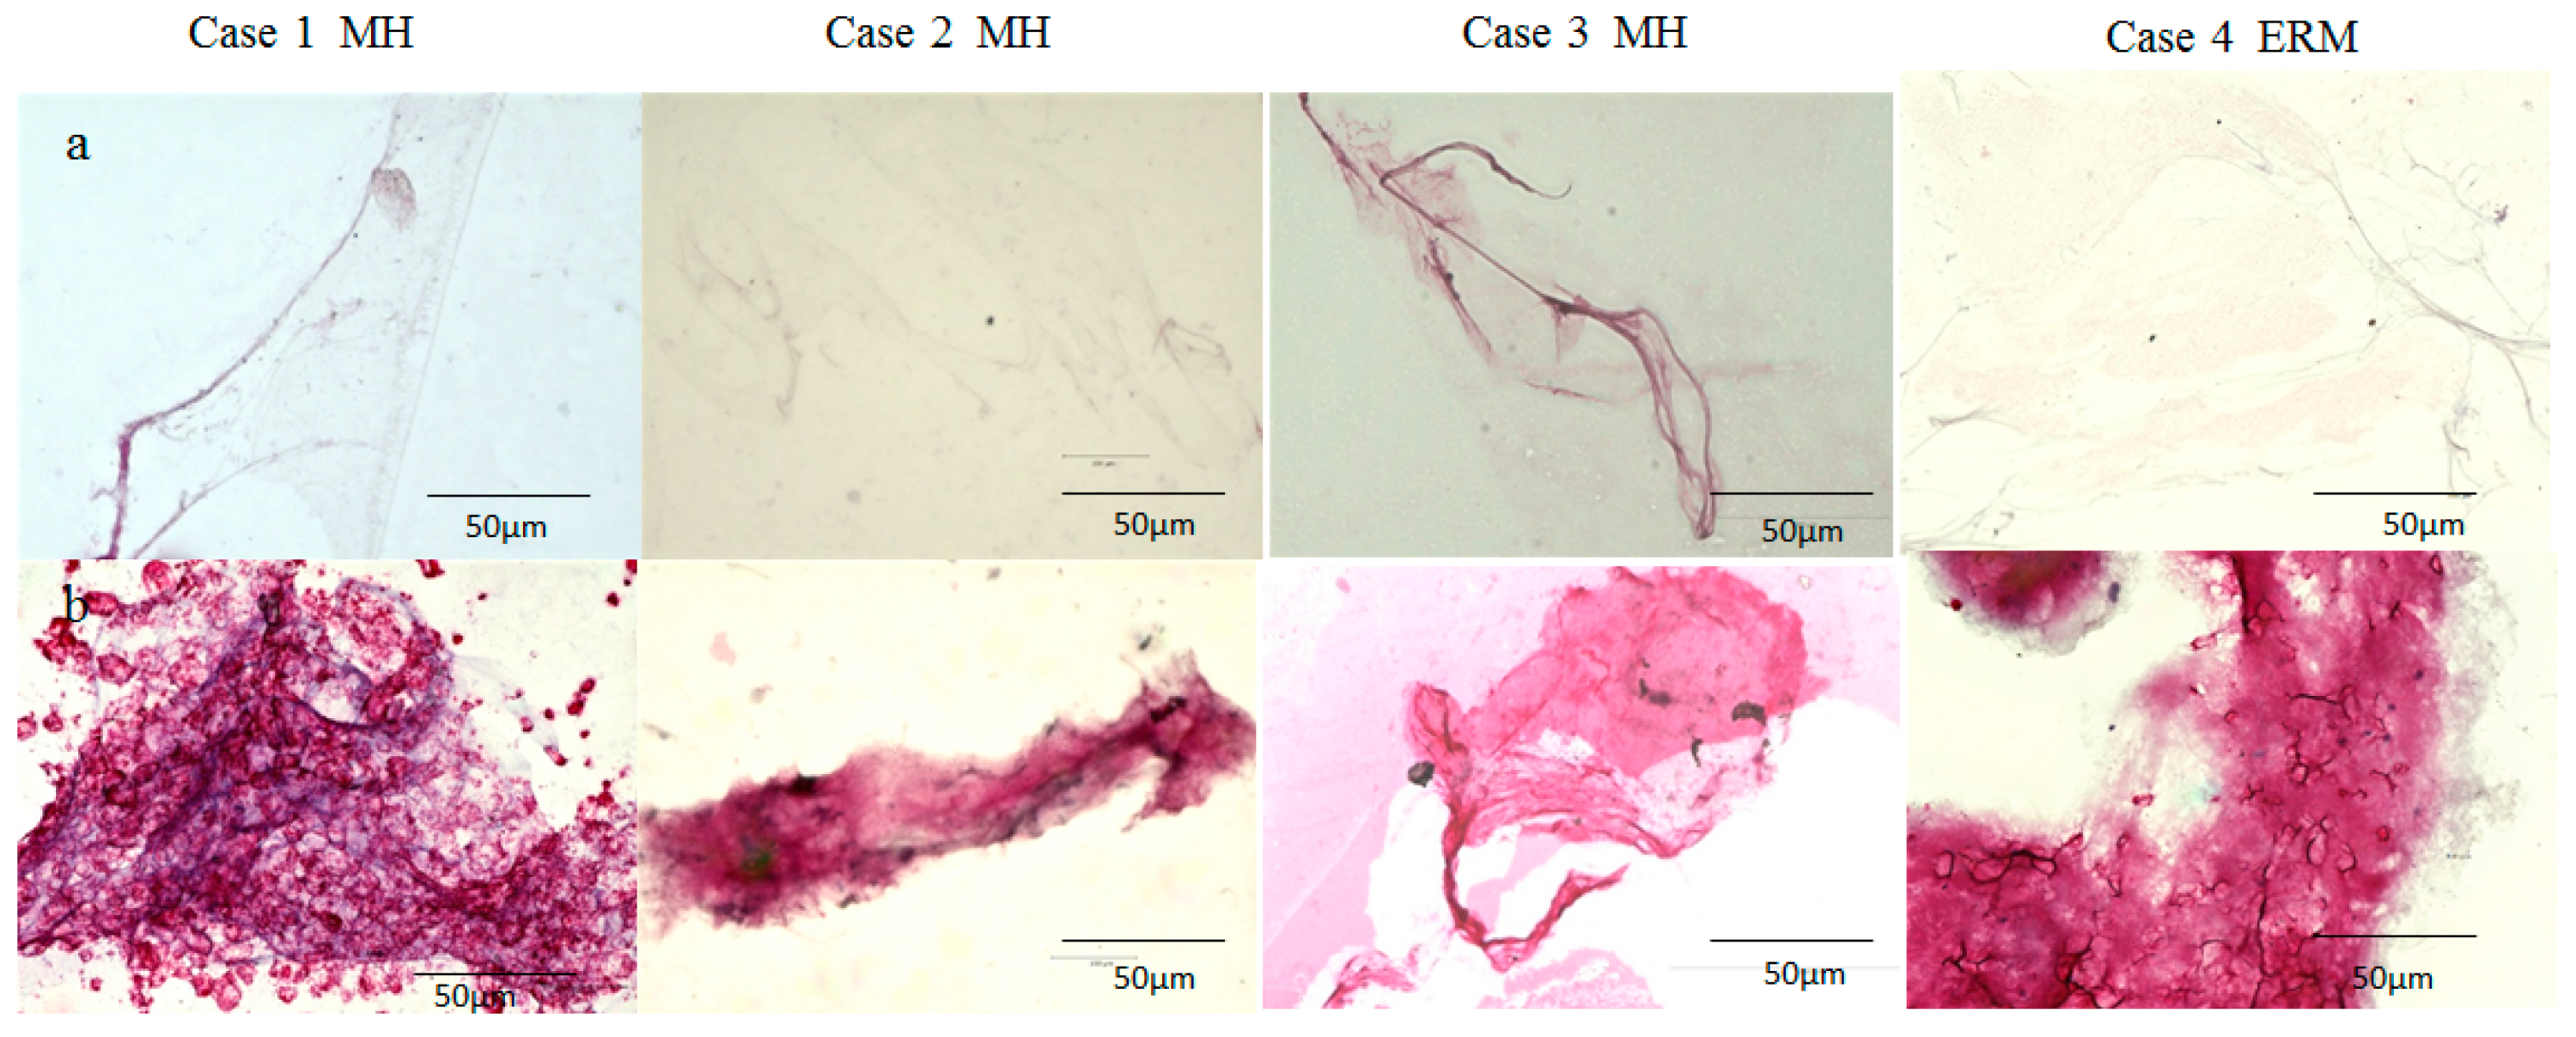

2.2. Immunostaining of the BPM and the Vitreous Core (VC) with Antibodies for Fibrillin-1 and -2

2.3. Immunostaining of the BS, BPM, and VC with Antibodies for Fibrillin-1 and -2, Podoplanin, and LYVE-1

4.2. Immunostaining of the BPM and VC with Antibodies for Fibrillin-1 and -2

4.3. Immunostaining of the BS, BPM, and VC Specimens with Antibodies for Fibrillin-1 and -2, Podoplanin, and LYVE-1